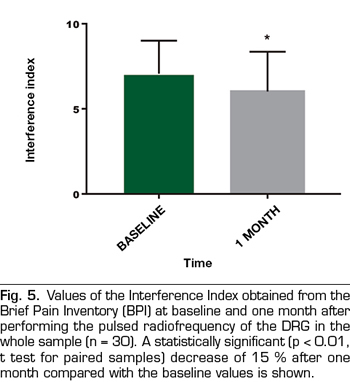

Results: The VNS score decreased from 7.7 ± 2,2 to 5.9 ± 3 (p < 0.01). Intensity and Interference Scores were reduced from 7.1 ± 1.5 to 5.9 ± 2.1 (p < 0.01) and 7.1 ± 1.9 to 6.0 ± 2.3 (p < 0.02) respectively. In 12 patients (40 %) a satisfactory analgesic response was observed. In these patients the VNS decreased from 8.0 ± 1.5 to 3.8 ± 2.6. Intensity and Interference Scores were reduced from 7.4 ± 1.3 to 3.9 ± 1.5 (p < 0.0001) y 7.7 ± 1.9 to 4.9 ± 2,7 (p = 0.002) respectively.

The score in the VNS prior to the procedure was reduced from 7.7 ± 2.2 to 5.9 ± 3 (p <0.01, t test for paired samples), taking into account the entire sample (n = 30), which implies a variation of 23% (Table I, Figure 3). The Intensity Index decreased from 7.1 ± 1.5 to 5.9 ± 2.1 (p <0.01), which implies a change of 16%, while the Interference Index decreased by 15% (7.1 ± 1.9 to 6.0 ± 2.3) (p <0.02) (Table I, Figures 4 and 5). When evaluating the patients who responded favorably using VNS, 12 out of 30 patients showed a decrease of at least 2 points on that scale, representing 40% of the sample. If we analyze these patients separately, we can observe that the initial values of VNS decreased from 8.0 ± 1.5 to 3.8 ± 2.6 after the procedure, which implies a reduction of 53% (Table II, Figure 6).

Numerous studies have examined the magnitude of the changes in the Brief Pain Inventory associated with different treatments, and the results have shown improvements of 1 to 3 points, depending on the treatment and the underlying pathology. The available information suggests that a change of 1 point in the interference score would be a reasonable objective for studies designed to identify clinically important minimum changes (13). In our group of patients, the Interference Index was reduced by 1.1 points.